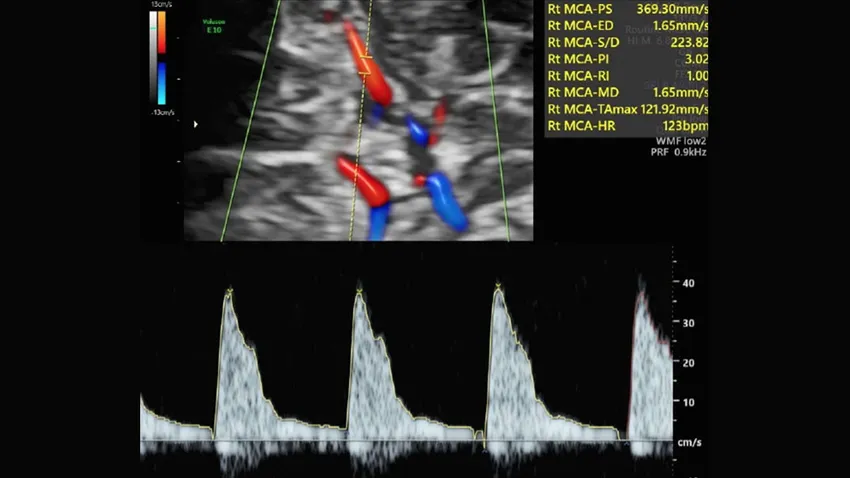

Una prueba con ecografía Doppler que mide la circulación de la sangre por el cordón umbilical y el cerebro, denominada ratio cerebro-placentario (o RCP), puede detectar la insuficiencia placentaria. Hasta ahora, esta prueba solo se realizaba en embarazos con problemas, en casos muy indicados. Desde hace más de 10 años ha existido un debate en el mundo científico sobre si había que medir el RCP en todas las embarazadas o era un gasto de recursos innecesario. Si la prueba Doppler se llevara a cabo en todos los embarazos, tal vez serviría para mejorar la detección de bebés con riesgo de complicaciones por insuficiencia placentaria. Pero también existiría el riesgo de que la prueba no mejorase nada y, en cambio, solo generase más gasto y angustia en las madres.

En el estudio RATIO37 han participado durante 6 años más de 11.500 mujeres con embarazos de bajo riesgo. En la ecografía de las 36 semanas se midió el RCP en todas las mujeres, pero las participantes fueron divididas al azar en dos grupos. En unas, la prueba se utilizaba para cambiar el manejo de la gestación y, en caso de salir alterada, se proponía a la mujer una inducción precoz del parto al llegar al término. En las otras, el resultado de la prueba no se comunicaba y se manejaba el embarazo según los protocolos vigentes. El estudio comparó los números de casos de muerte del bebé y de complicaciones neonatales graves (que incluían, entre otros, problemas neurológicos, intestinales, cardíacos, renales o respiratorios, con una estancia en la UCI de 10 días o más) que se producían en cada grupo.